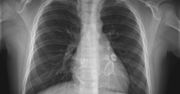

5-letnia Scarlett Nicholas z Wielkiej Brytanii najpierw zachorowała na COVID-19, a później na chorobę Kawasakiego, która według lekarzy jest powiązana z koronawirusem. Dziewczynce dawano 20 proc. szans na przeżycie, a jej rodzicom kazano przygotować się na najgorsze. Na szczęście 5-latka wygrała z chorobą. To nasza #DziennaDawkaDobregoNewsa.